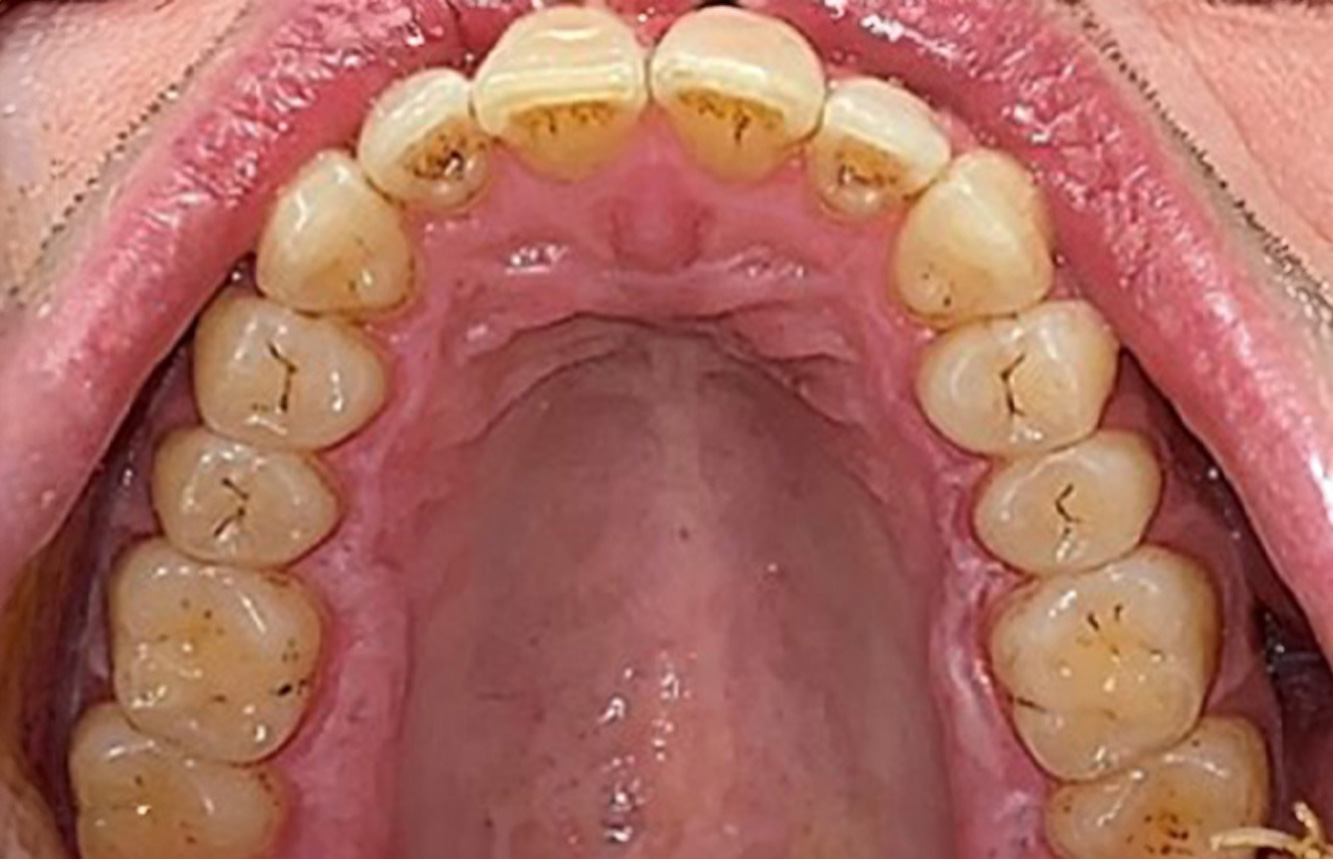

Următoarele studii de caz* acestea au rolul să ilustreze interacțiunea dintre necesitățile și factorii de risc definiți pentru IPC, precum și efectele factorilor individuali.

Pacient diabetic cu o bună sănătate

O pacientă diabetică de 51 de ani, cu o bună sănătate orală, se prezintă pentru o ședință de profilaxie. Glicemia este stabilă la HbA1c = 6.2%, prin urmare, se consideră că starea ei este suficient de bine gestionată cu medicamentul antidiabetic metformin. Pacienta nu prezintă lucrări dentare sau patologie orală. Cu ajutorul rezultatelor dentare, este posibilă determinarea gingivitei în ciuda condițiilor de altfel stabile. mai multe